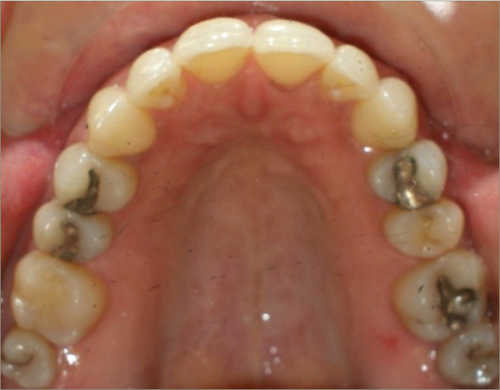

32 year old female:

Diagnosis:

- Previously lost upper first molars

- Severe lower arch crowding

- Midline discrepancy

- Narrow upper arch form

Treatment:

- Extraction of lower right first bicuspid

- Substitution of upper second molars for first molars

- Full fixed appliances

- 23 months